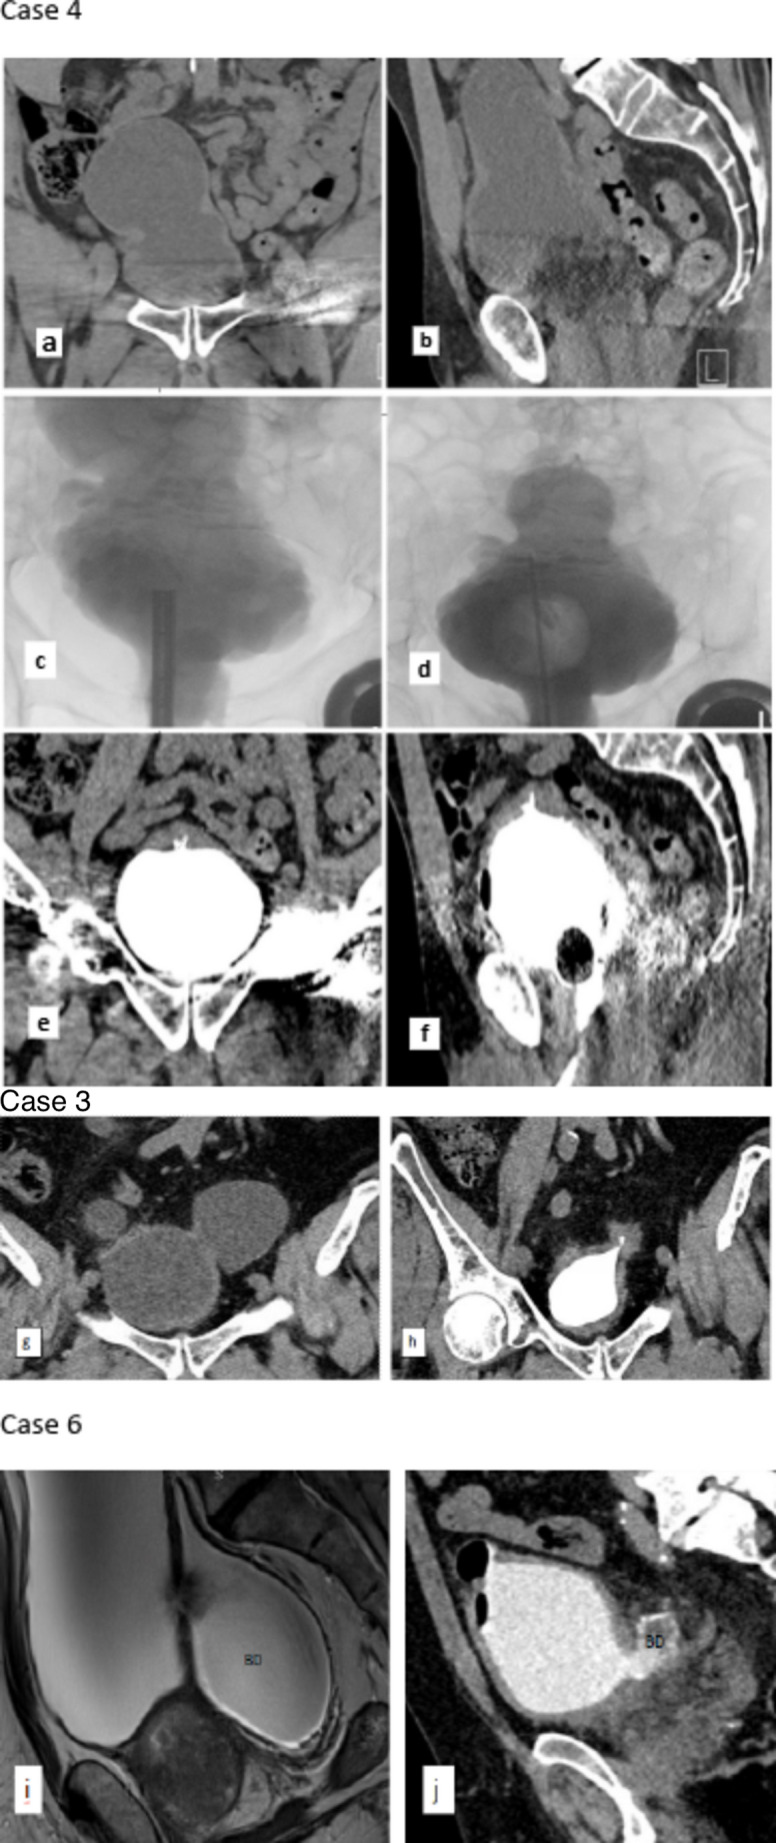

Methods: We retrospectively reviewed patients who underwent combined HoLEP with transurethral endoscopic management of bladder diverticulum (C-HoLEP-TUBD) between May 2017 and January 2025. Following HoLEP, the diverticular neck was circumferentially resected, and the diverticular mucosa was fulgurated using bipolar cautery. Follow-up cystography was obtained 6-12 weeks postoperatively and perioperative data were collected and analyzed.

Results: Six patients (mean age: 72 + 7.46 years) underwent the procedure. The mean prostate volume was 91 ± 43 cc, and mean BD size was 8.57 ± 5.28 cm. Preoperative Qmax averaged 4.76 ml/s, and mean post-void residual (PVR) was 372.8 cc. At 3-month follow-up, Qmax improved to 25.74 ± 22.4 ml/s, and PVR decreased to 22 ± 23.24 cc. Mean diverticulum size reduced to 1.7 ± 1.19 cm, representing an of 81.89 ± 15.09% reduction. No patient had a residual diverticulum > 2 cm or developed related symptoms during follow-up.